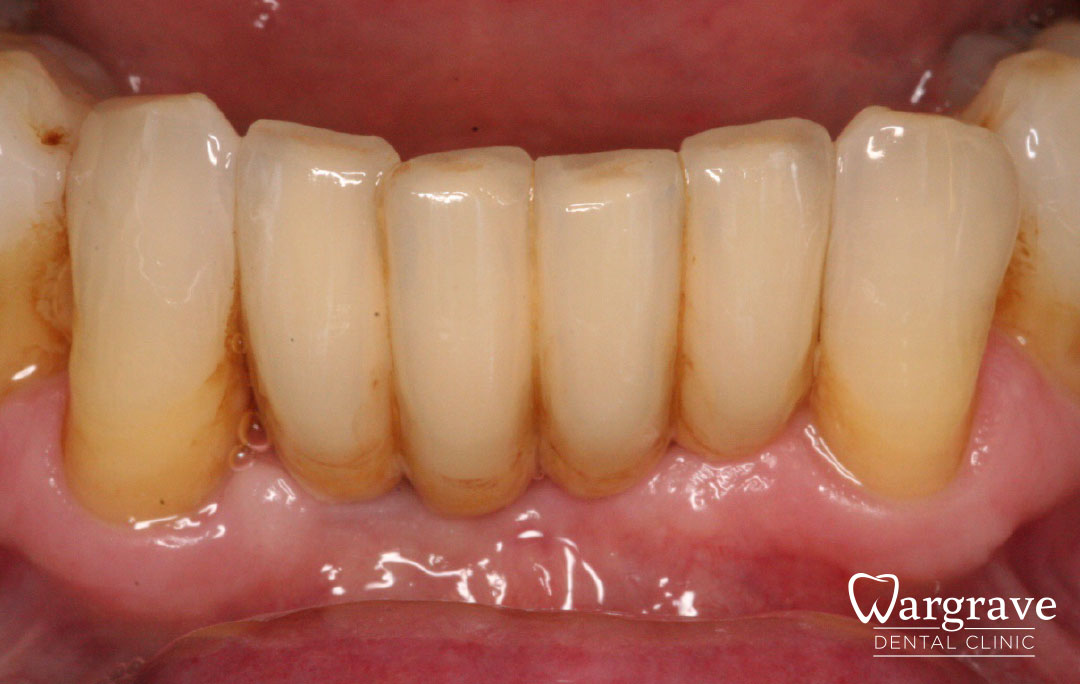

Healthy Smiles These are more advanced examples of different treatments available.All cases shown were carried out by Dr R Khurana unless otherwise stated. Immediate implants Anterior Mandible Bone Regeneration Anterior Mandibular Implant Bridge Maxillary Anterior Implant Bridge Implant stabilised ‘Life Like’ replacement dentures Implant Bridge after 10-years with zero bone loss Implant examples including ZBLC concepts Adhesive Bridge solution for a missing premolar Multidisciplinary care Orthodontics, Replacement veneers and composite bonding Adhesive Bridge solution for missing central incisors Replacement crown, Veneer and Composite Bonding Replacement Crowns and Veneer Injection Moulding using Composite Resin Equilibration Tooth Whitening to treat Developmental Discolouration